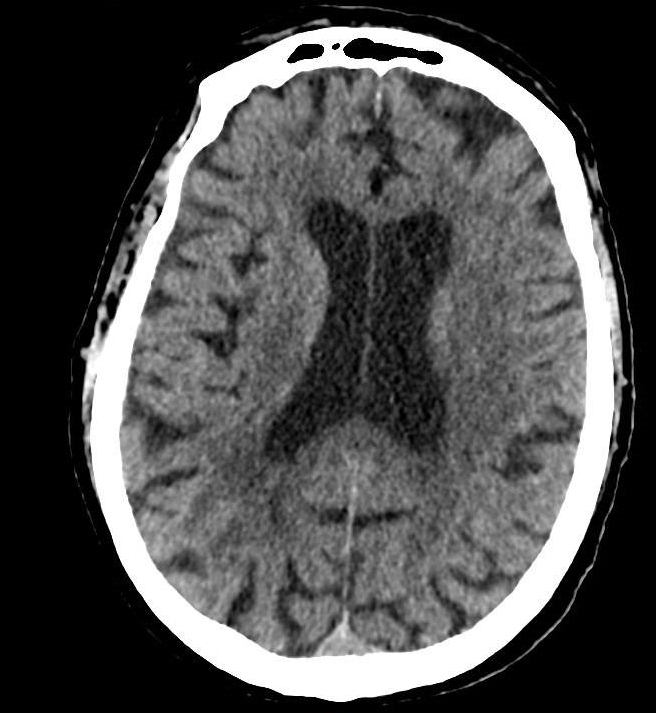

Il s’agit de céphalées matinales d’évolution progressive depuis un mois devant faire évoquer une hypertension intracrânienne et toutes ses causes (y compris une thrombose veineuse cérébrale), une méningite chronique, une hypertension artérielle incontrôlée, ou une artérite a cellules géantes.